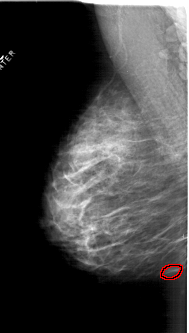

A_1814_1.LEFT_CC

LEFT_CC LINES 6451 PIXELS_PER_LINE 3496 BITS_PER_PIXEL 12 RESOLUTION 43.5 OVERLAY

FILE: A_1814_1.LEFT_MLO.OVERLAY

TOTAL_ABNORMALITIES 1

ABNORMALITY 1

LESION_TYPE MASS SHAPE OVAL MARGINS CIRCUMSCRIBED

ASSESSMENT 3

SUBTLETY 3

PATHOLOGY BENIGN

TOTAL_OUTLINES 1